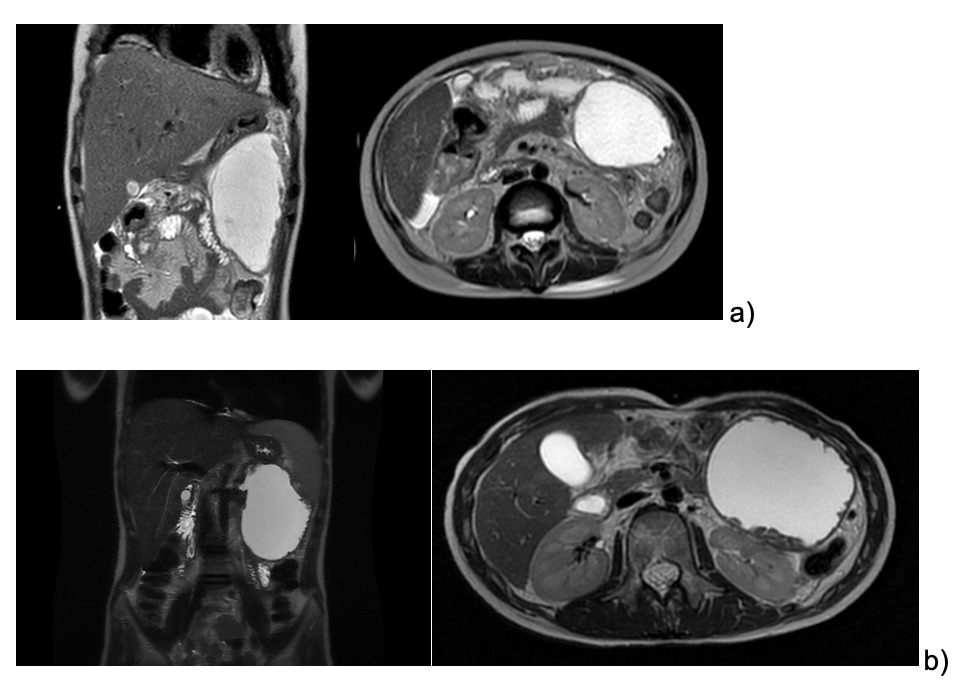

We describe the case of an 11 year-old female patient affected by pre-B ALL treated according to the early non-high-risk group in AIEOP-BFM-2017 protocol. One week after the start of Protocol Ia, a staging brain MRI showed cerebral venous thrombosis, which was treated with intravenous heparin for three weeks, followed by subcutaneous injections. The patient received two doses of PEG-asparaginases on days +12 and +26, and on day +48 she presented at the Emergency Department complaining of epigastric abdominal pain worsening after meals. Blood tests showed increased pancreatic enzymes (lipase 1383 U/l, amylase 310 U/l) and coagulation alterations (PT ratio 1,22, aPTT 1,09, Fibrynogen 111 mg/dl, Antithrombin 31%, D-Dimer 1087) suggesting acute pancreatitis, which was confirmed by a CT scan showing enlarged pancreas volume with multiple hypointense areas of necrotizing pancreatitis associated with local thrombosis of the distal splenic vein, and peritoneal and pleural effusions. A nasogastric tube was positioned and fasting started. After a few hours, her general conditions precipitated into a septic-like shock state, requiring fluid boluses, albumin, fibrinogen, antithrombin III, and broad-spectrum empirical antibiotics. Echocardiography showed mild pericardial effusion and signs of myocardial injury. The clinical and laboratory manifestations progressively resolved during the following days. After two weeks, an abdominal MRI revealed the initial formation of a non-encapsulated pancreatic fluid collection along the left side and hypochondrium, measuring 13 x 7 x 7 cm (Fig.1a).

The patient continued to refer mild abdominal pain, and a cholangio MRI confirmed the persistency of an encapsulated pancreatic fluid collection without size reduction (Fig.1b). After a multidisciplinary discussion, the decision was made to perform an endoscopic-ultrasound (EUS) guided cystogastrostomy with a 10 x 10 mm lumen-apposing metal stent (LAMS) (Hot-Axios™ system) under general anesthesia. During the procedure, after the release of the LAMS, a 7 cm x 7 Fr double-pigtail plastic stent (DPPS) was coaxially released (Fig.2); the post-operative course was uneventful and the patient was discharged after 48 hours. Seven days thereafter, an abdominal ultrasound confirmed the complete resolution of the PCF, the LAMS was removed, and a “soft” DPPS 7 cm x 10 Fr (Solus-Cook®) was positioned endoscopically in the cystic cavity under endoscopic and radiological control (Fig.3). The patient was dismissed the following day without any complications, and two weeks thereafter she restarted the AIEOP-BFM-2017 protocol at Short Consolidation B, 4 months after the interruption of the consolidation phase. No pancreatic fluid collection was observed at the following abdominal ultrasounds, the latest performed 7 months after interventions, together with an abdominal x-ray that showed the persistent presence of the double pig-tail. The prosthesis removal will be scheduled together with the central venous catheter removal at the end of the maintenance phase, due in a few months, so as to perform a single sedation.

_abdominal_mri_14_days_after_aap__b)_cholangio_mri_3_months_after_aap.png)